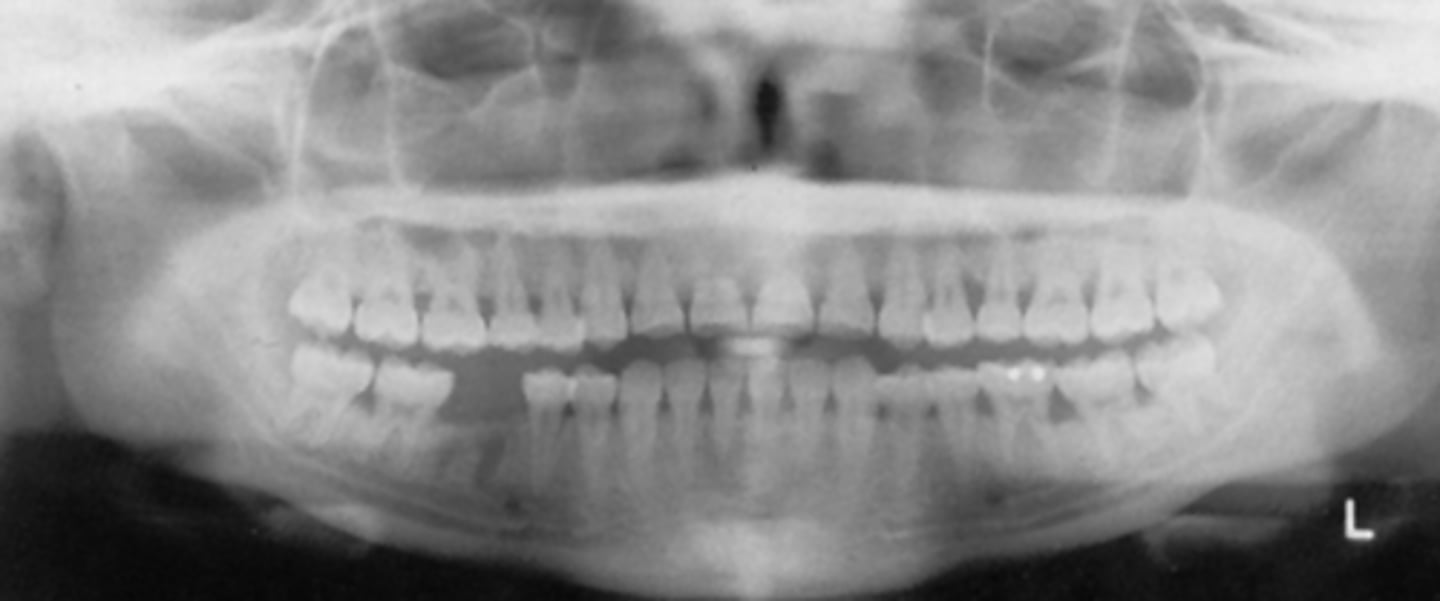

The curve of the image is slightly flat, which means the chin was slightly ___

A) up

B) down

If the pan image appeared too smiley, the patient's chin was too far ___ (image is just a placeholder and not necessarily related to this question)

If the pan image appeared too frowny, the patient's chin was too far ___ (image is just a placeholder and not necessarily related to this question)